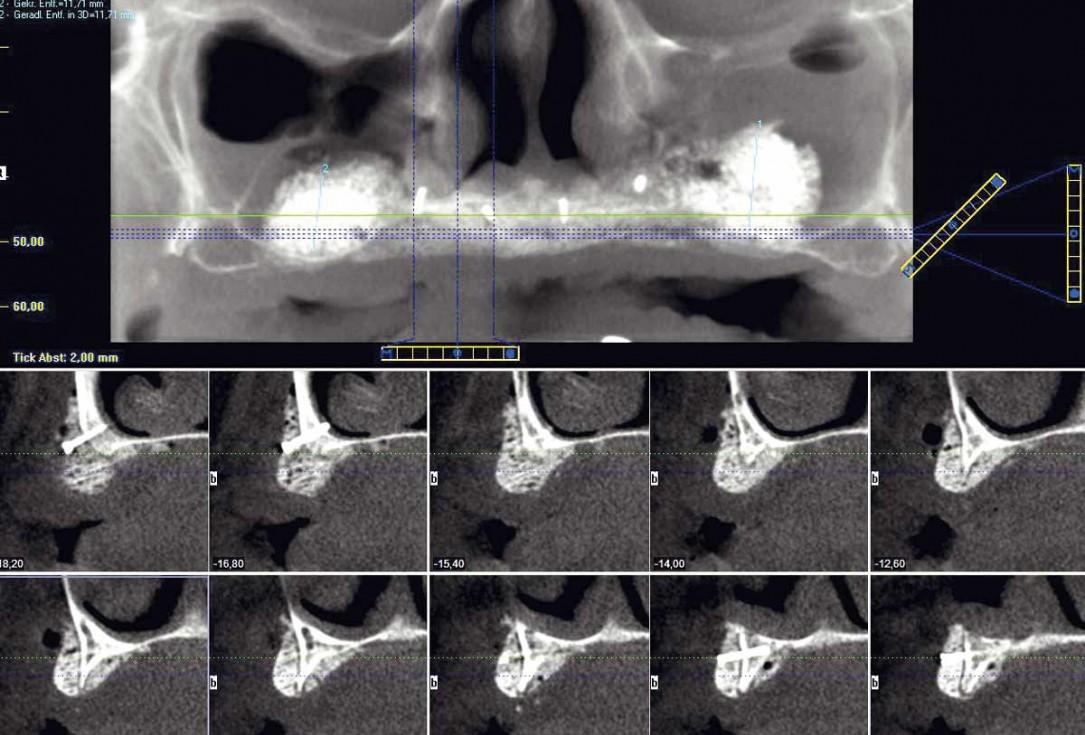

2/23 - Preoperative radiological situation – severely atrophic maxilla

Full arch reconstruction of the maxilla with maxgraft® bonebuilder - Dr. M. Erbshäuser